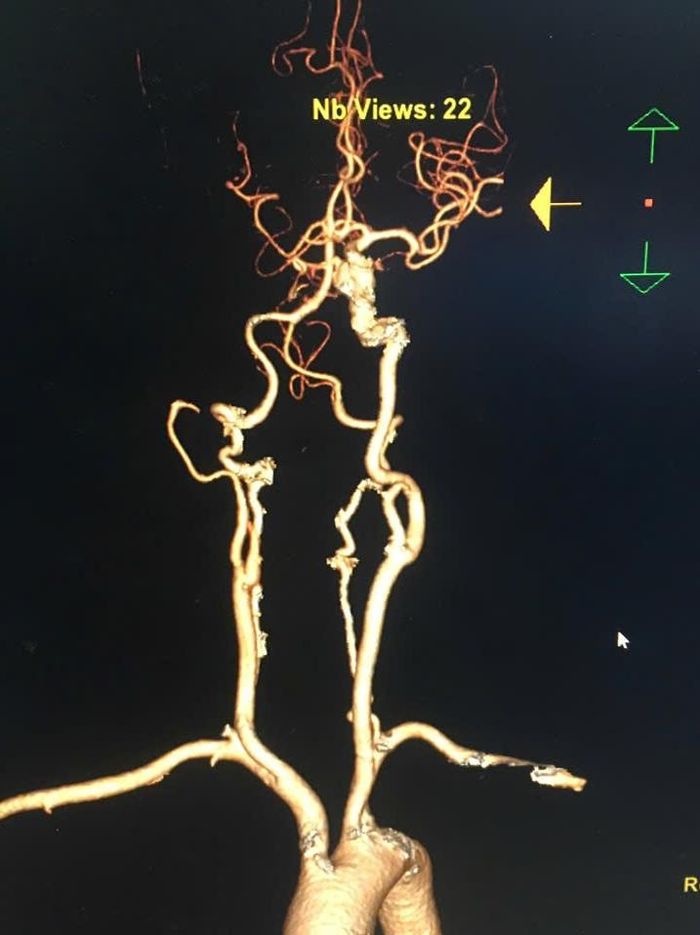

Hình ảnh bệnh nhân bị tình trạng tắc mạch máu lớn - dạng đột quỵ nguy hiểm.

Tại Trung tâm can thiệp tim mạch - Bệnh viện Đa khoa tỉnh Quảng Ninh, bệnh nhân được chỉ định chụp mạch não cấp cứu. Kết quả chụp cho thấy có hình ảnh tình trạng tắc mạch não lớn - dạng đột quỵ nguy hiểm, thường không thể chỉ điều trị bằng thuốc tiêu sợi huyết. Bệnh nhân đã được can thiệp lấy huyết khối cơ học thành công, tái thông dòng chảy não và mở ra cơ hội hồi phục rõ rệt.